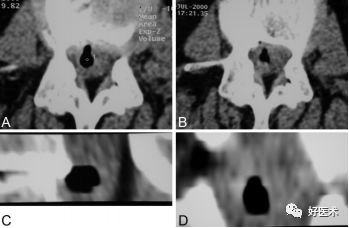

图示:谭军教授团队提出的颈椎间盘突出的形态学分型示意图